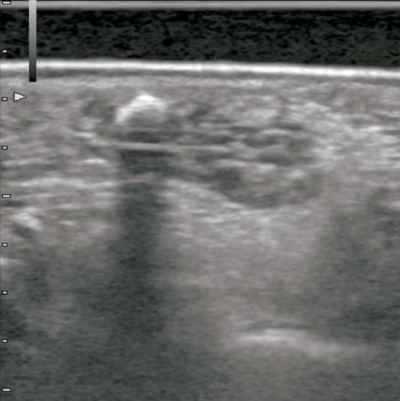

40 歳の女性。舌の腫脹を主訴として来院した。舌背部に弾性軟の無痛性腫脹を認める。初診時の口腔内写真、CT、MRI 脂肪抑制T2 強調像及び口腔内超音波検査の画像を別に示す。考えられるのはどれか。1つ選べ。